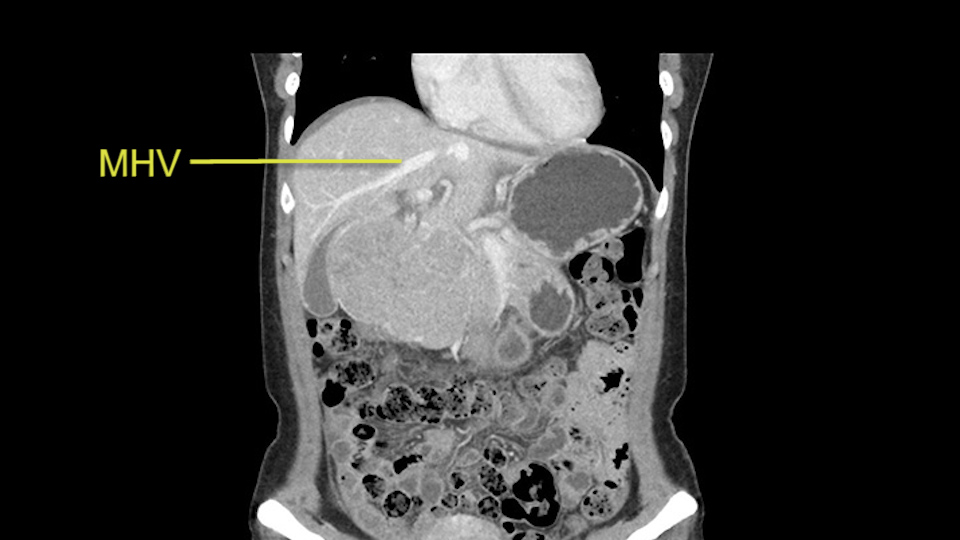

Anatomically, to plan for a left lateral segmentectomy, it’s relatively easy as far as liver surgery goes. I know that I'm going to be looking for the left hepatic vein which will be divided at some point either towards the end at the back near the vena cava or through the middle of the left lateral segment.

Preserve middle hepatic vein

The transection line will be a little more obvious. There’s a little patch of focal fat here in Segment 4b but we’ll describe the transection line probably through the mid portion of Segments 4a and b up to the top. Up at the top, the left hepatic vein can be taken. There’s a Segment 3 vein or the so-called falciform vein it’ll be rudimentary so I think we’ll be able to get around the left hepatic vein and leave the middle [hepatic] vein intact because it’s free of tumor.

Her vein, it looks like a combined middle and left hepatic vein, it may be encircled during the case as a whole common trunk but most probably it will not be a big deal because if it is okay to go with the left lateral resection, the vein or the left hepatic vein can be catched during the intraparenchymal dissection and can be controlled in that side.

So in terms of planning on the surgery, I think there’s two clear options for this patient and that we’ll need to assess once we’re in the operating room. One option would be to do a Segment 3 resection. This tumor seems like it's hanging from Segment 3 so I think if we can get a good margin, that would be an option. Of course the other option is to do a left hepatectomy, preserving the middle hepatic vein, which is clearly not involved with the tumor.

The other option of course is to do an anatomical left hepatectomy. In that case, I will start mobilizing of course the left lobe and try to find the ligamentum venosum, take it down and go around the left hepatic vein. I think, importantly in these cases and in this case, as you can see in the venous phase, that’s clearly a moment to stop. Because the left hepatic vein is pretty close to the middle hepatic vein as sometimes it is so you may need to dissect a little bit the parenchyma on top of the left hepatic vein to be able to go around the left hepatic vein safely.